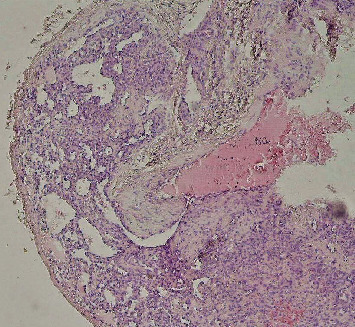

中枢性血管瘤是一种罕见的颌骨病变,患病率在0.5%至1%之间。它更常见于脊柱和颅骨,很少发生在颌骨。世界卫生组织将血管瘤归类为真正的内皮源性肿瘤;然而,一些作者认为血管瘤是错构瘤。由于其不同的临床和影像学特征,这种病变的诊断可能具有挑战性。由于受影响区域存在广泛的血管网络,治疗也很困难。在这篇文章中,我们提出了一个57岁女性颧骨中央血管瘤的病例,通过手术切除治疗。

Central hemangioma is one of the rare lesions of the jawbones, with a prevalence ranging between 0.5% and 1%. It more commonly occurs in the vertebral column and cranial bones, with rare occurrences in the jaws. The World Health Organization classifies hemangioma as a true neoplasm of endothelial origin; however, some authors believe that hemangiomas are hamartomas. Diagnosis of this lesion can be challenging due to its varying clinical and radiographic characteristics. Treatment is also difficult due to the presence of an extensive vascular network in the affected area. In this article, we present a case of central hemangioma in the body of the zygomatic bone of a 57-year-old female, which was treated through surgical resection.